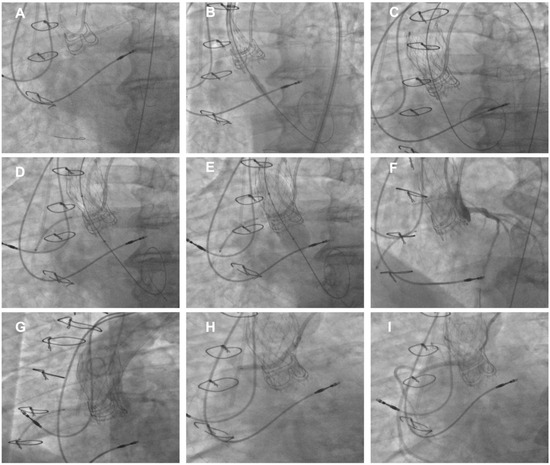

Figure 4. Example of TAV-in-SAV at high risk of coronary obstruction. (A) Cannulation of both LCA and RCA using double-radial 6Fr approach. (B) Placement of guide extension catheter in RCA before deployment of Evolut Pro+ 23 THV in degenerated CE Magna 3000 21. (C) Final deployment of Evolut PRO+ 23 THV. (D) Undeployed drug-eluting stent positioned in RCA before post-dilatation. (E) Post-dilatation using non-compliant balloon. (F) Angiography showing good perfusion of both LCA and left sinus. (G) Aortogram showing impaired perfusion of RCA and right sinus while LCA is perfused. (H) Pull back and deployment of stent with its proximal portion positioned above neoskirt using chimney technique. (I) Final angiography showing good RCA perfusion. SHV: surgical heart valve; THV: transcatheter heart valve; ViV: Valve-in-Valve.